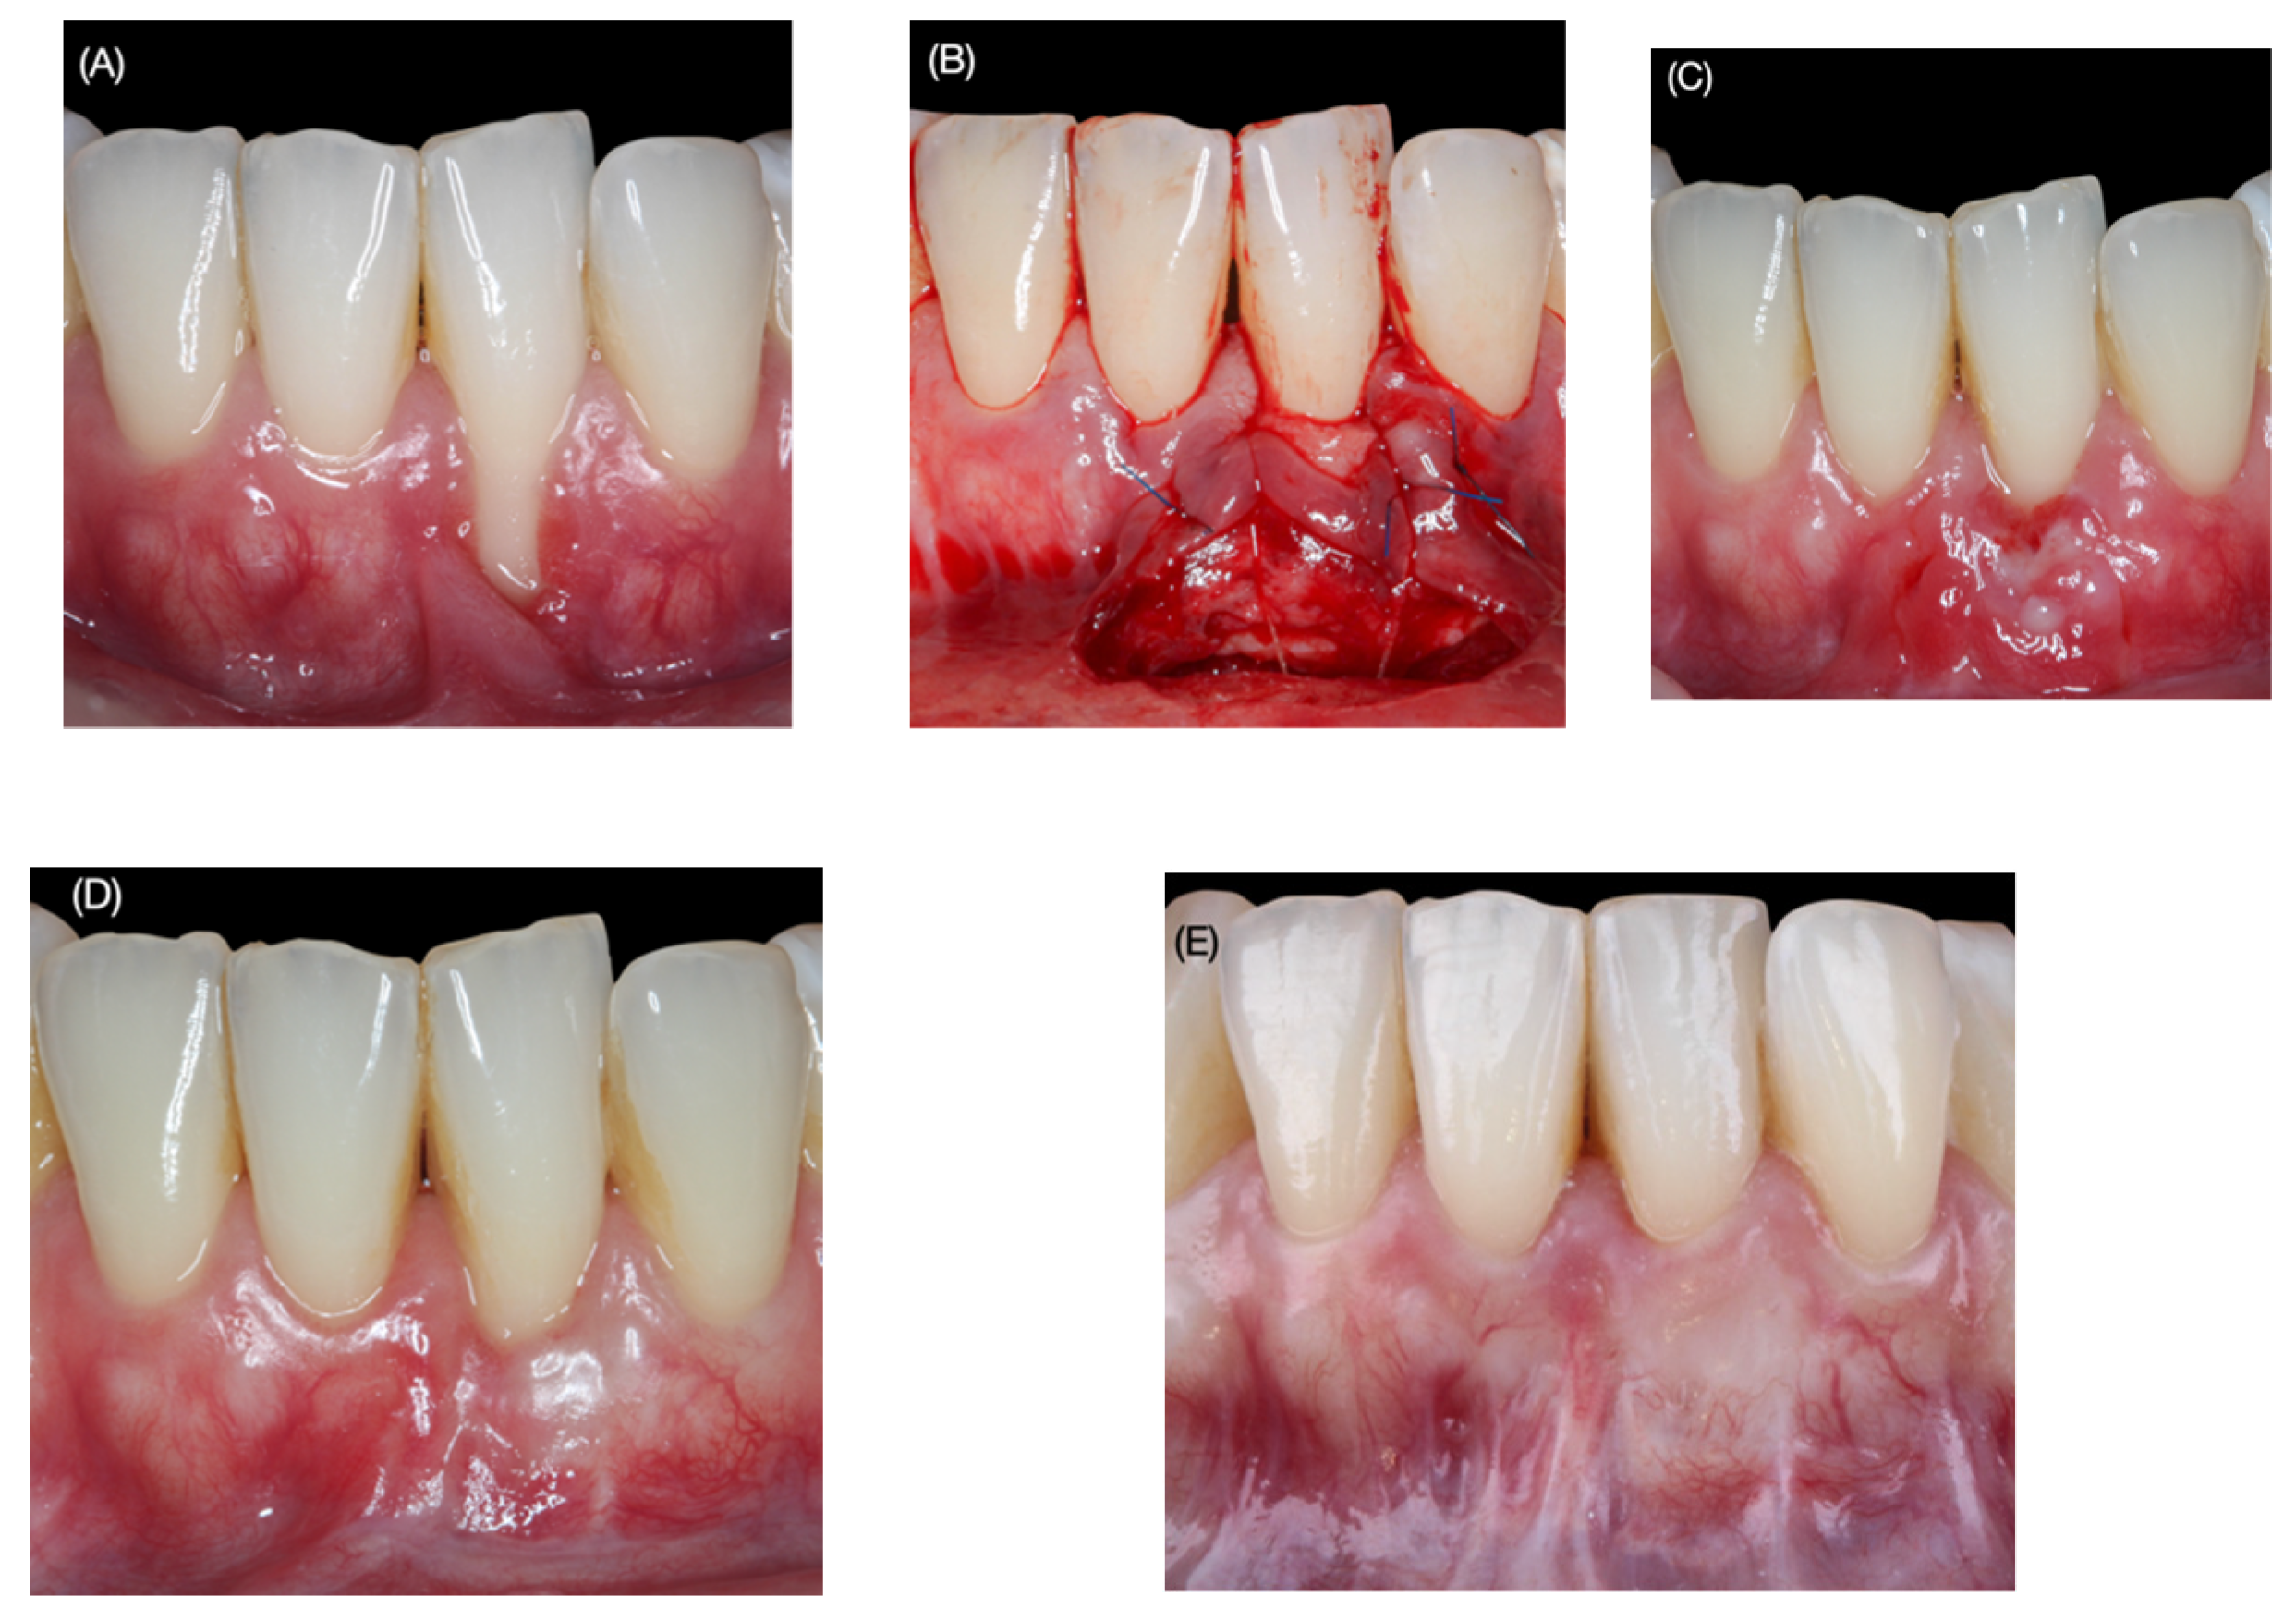

2.1. Surgical Protocol